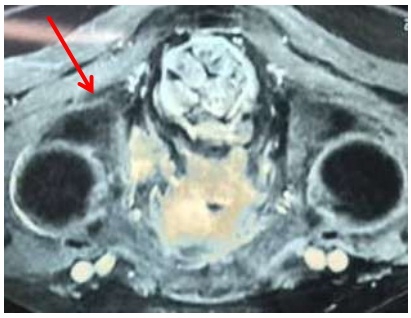

Chụp cộng hưởng từ tiểu khung có hình ảnh u tuyến tiền liệt xâm lấn thành bàng quang và túi tinh bên trái, di căn hạch chậu.

Hình ảnh cộng hưởng từ: tuyến tiền liệt nhu mô không đồng nhất, ngấm thuốc mạnh sau tiêm thuốc, ranh giới không rõ, xâm lấn thành sau bàng quang và túi tinh trái (mũi tên).